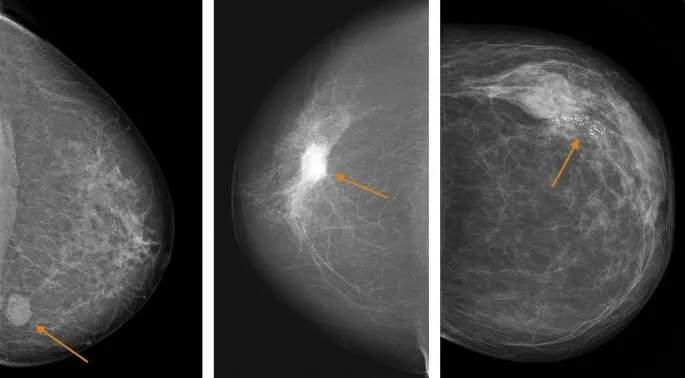

Mammography Lexicon - Finding Clues

Key descriptors:

Masses:

- Shape: Round, Oval (often benign); Irregular (suspicious).

- Margin: Circumscribed (benign); Obscured, Microlobulated, Indistinct, Spiculated (suspicious).

- Density: Fat-containing, Low, Equal, High (vs. fibroglandular tissue).

⭐ Spiculated margins on a mammographic mass are highly suspicious for malignancy.

Calcifications: Morphology & Distribution:

Type Benign Examples Suspicious Examples Morphology Round, Popcorn, Vascular, Large rod-like, Rim Pleomorphic, Fine linear/branching, Amorphous, Coarse heterogeneous - Distribution: Diffuse, Regional, Grouped (>5 calcs in <1 cm area), Linear, Segmental.

Architectural Distortion: Parenchymal distortion (radiating lines) without definite mass.